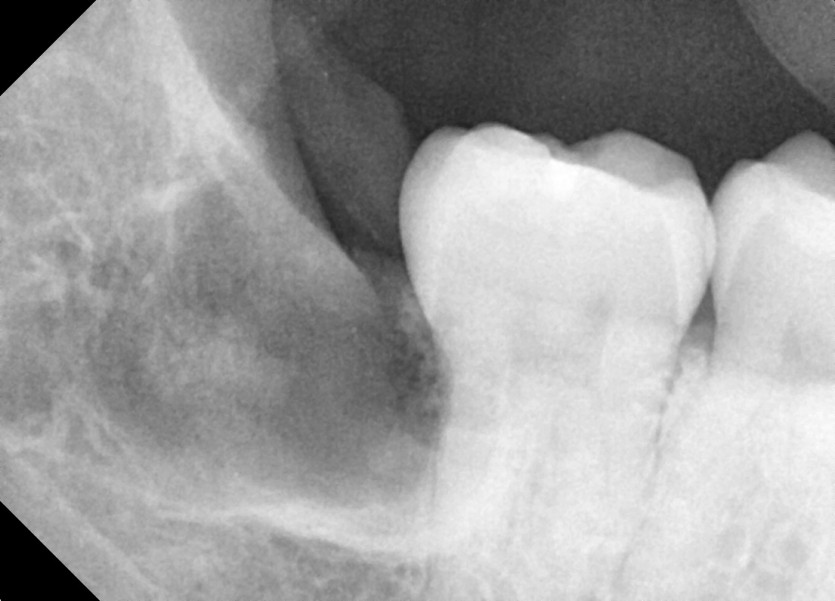

#48 사랑니 발치

구강 외과 전문의가 당일 발치했습니다.